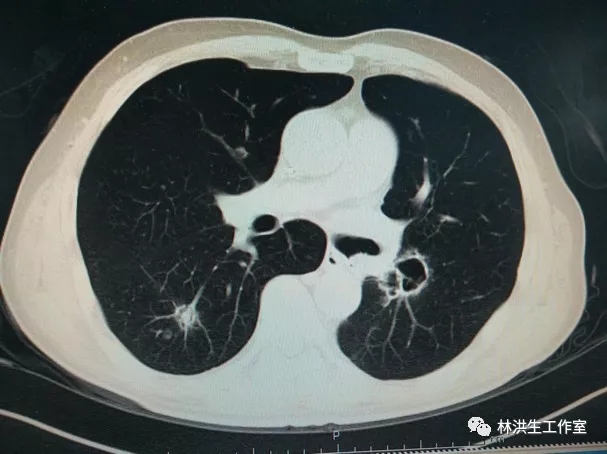

【诊断】右肺腺癌术后,左肺门及纵膈淋巴结转移,多程化疗后 Ⅲ期

【现病史】患者2011年8月诊断右肺上叶中低分化腺癌Ⅲ期,行右肺上叶切除术后行5周期GP方案辅助化疗,后定期复查胸部CT,病情稳定。2015年1月22日胸部CT提示:右肺下叶近肺门可见形态不规则肿物影,大小约3*3.5cm,纵膈及左肺门可见多发淋巴结影,考虑进展,予中西医结合治疗至今,病灶控制稳定,体力状况PS 100分。

2017-10-21中药治疗后:双肺多发转移瘤大者增大至约2.6*2.3cm